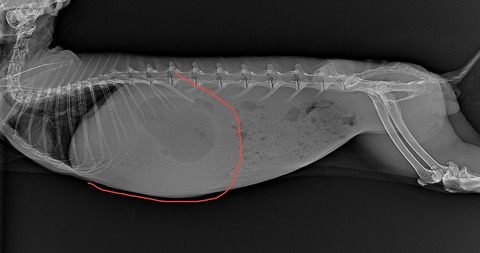

胃拡張になると、最後肋骨を大きく越えてきます

(⇩急性胃拡張)